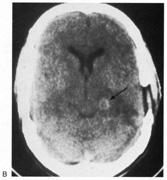

Fig. 16. CT scan of man with cerebral blindness after a gunshot wound.